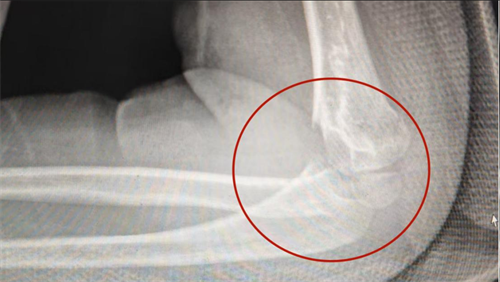

在医院康复医学科诊室,副主任医师陈琛检查发现,李远的左肘关节弯曲只能到95°(正常 150°),伸直卡在 50°(正常 0°),活动范围不足正常三分之一,如同生锈的门轴被死死卡住。结合X 光片明确诊断为“创伤后肘关节僵硬”。